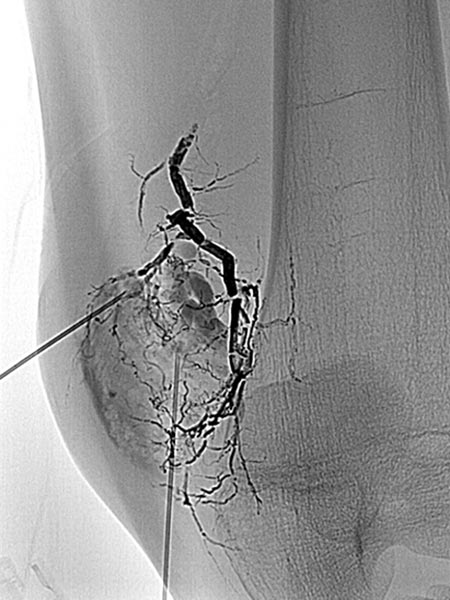

Die digitale Subtraktionsangiographie (DSA) in der früharteriellen Phase zeigt eine, aufgrund der chronischen Mehrdurchblutung erweiterte, zuführende Arterie (sogenannte Feederarterie), in diesem Fall eine Arteria genu superior medialis.

Die digitale Subtraktionsangiographie (DSA) in der arteriellen Phase 2 s später zeigt einige kleinere arteriovenöse Fisteln.

Die digitale Subtraktionsangiographie (DSA) in der arteriellen Phase zeigt im Gegensatz zu einer arteriovenösen Malformation nochmals 4 s später keinen direkten frühvenösen Abstrom des Kontrastmittels, sondern eher ein Pooling-Phänomen.

Superselektive Sondierung der Arterie mit einem Mikrokatheter zeigt wiederum die multiplen, feinen arteriovenösen Fisteln, jedoch nicht den für eine AVM typischen sofortigen venösen Abstrom. Diese starken arteriovenösen Fisteln in die VM sind ungewöhnlich ausgeprägt.